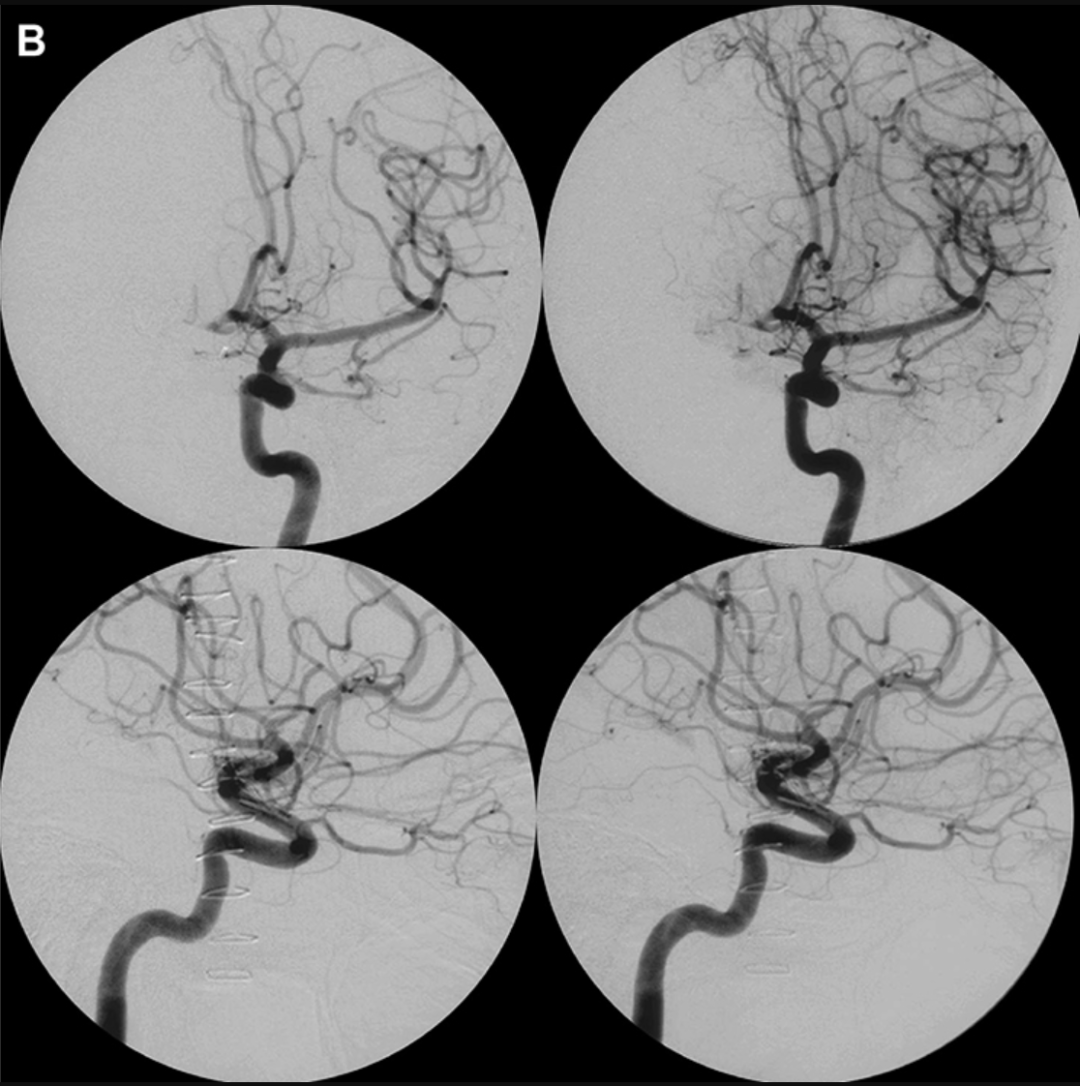

术后影像

术后血管造影显示大部分AVM病灶已切除,动静脉分流明显减少,右侧大脑前动脉存在小的残余供血。